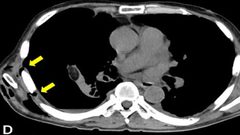

تضخم فقاعة هوائية تحت الجلد يسبب آلاماً شديدة